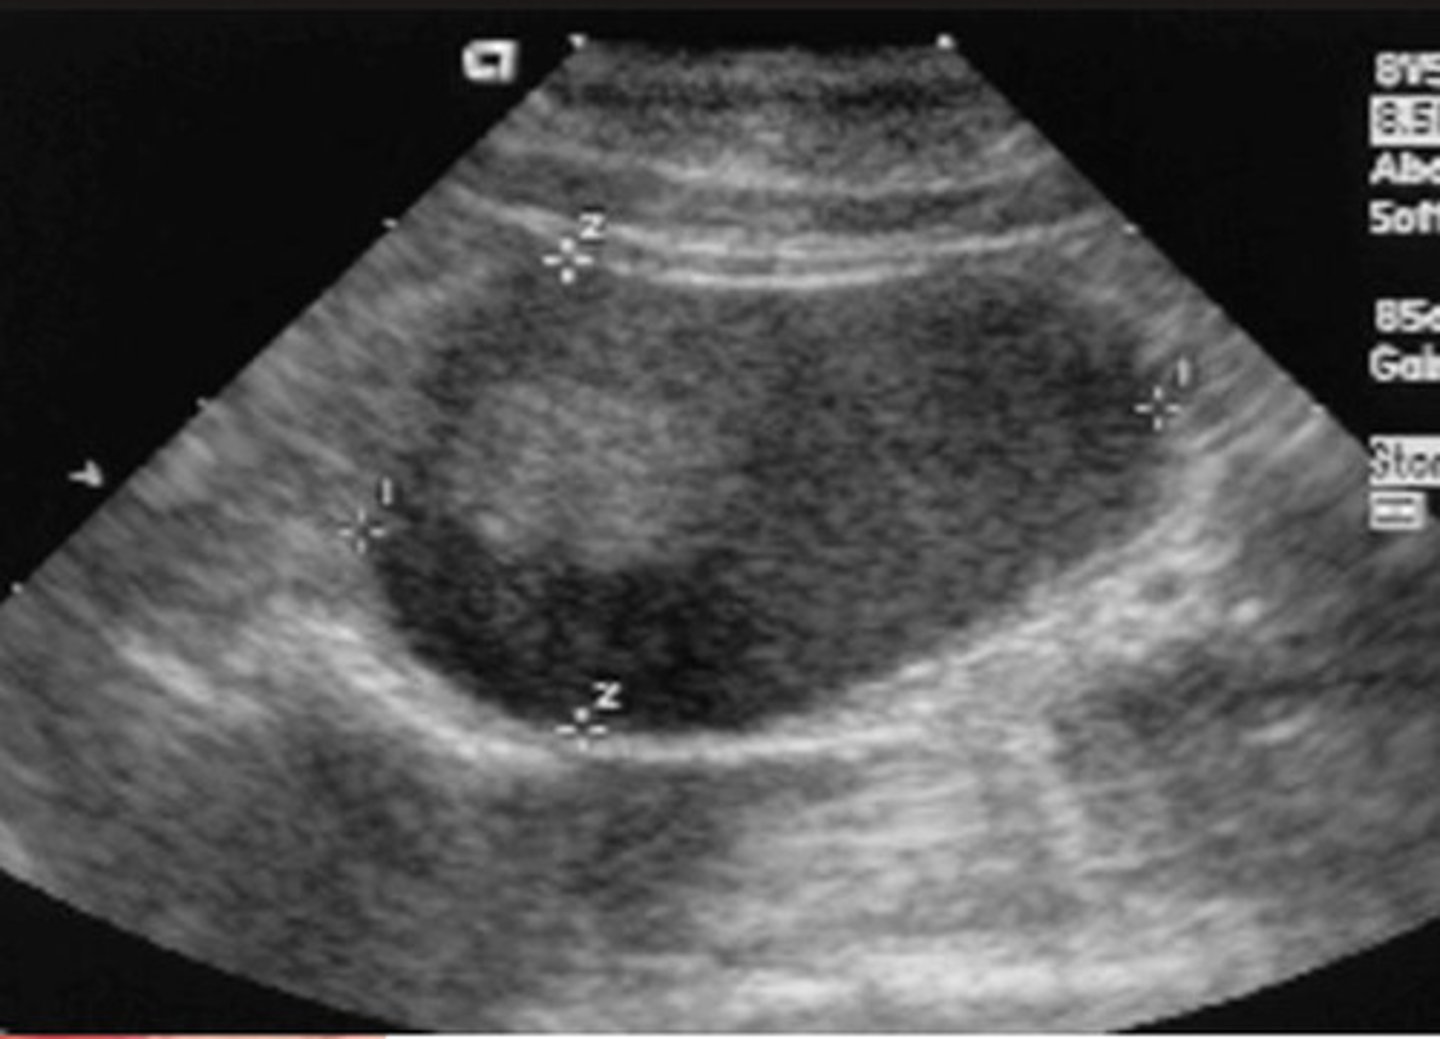

A- aorta

EI- external iliac artery

II- internal iliac artery

ID vasculature on US